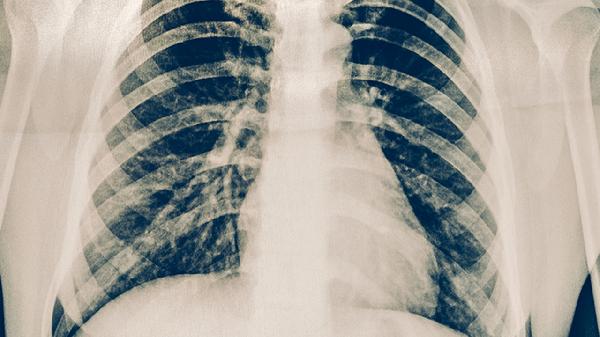

3、X线检查

X线检查主要用于排除肋骨骨折、肺部疾病或胸椎病变等相似症状疾病。典型肋软骨炎在X线下多无异常表现,因为肋软骨在X线下不显影。这项检查对鉴别诊断具有重要意义,可帮助确认肋软骨炎的诊断。